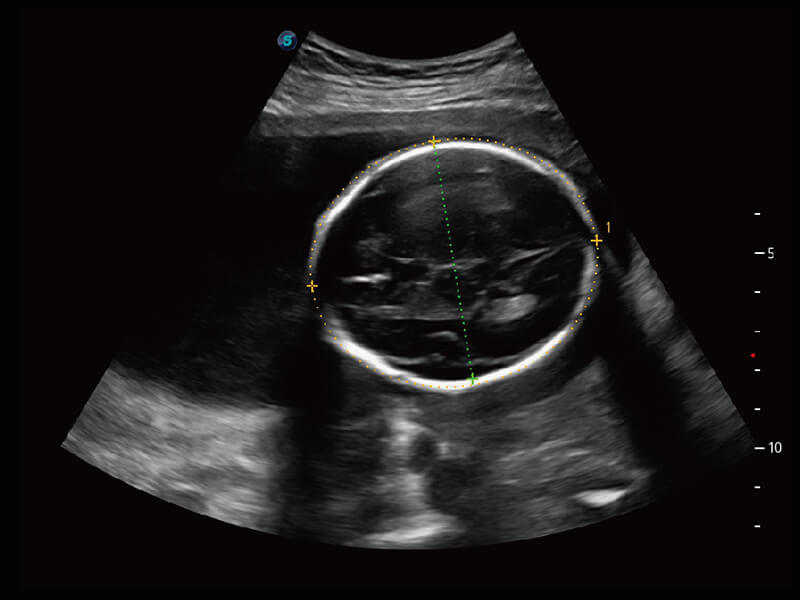

成像功能

S60探头工艺,从前端信号处理每一个环节采集无损声学数据,真实还原组织原貌,再现解剖细节。

超宽频带技术,为容积成像带来优质的二维图像基础,为您呈现丰富的结构细节,栩栩如生地展示宝宝的宫内形态以及各种组织的立体结构。